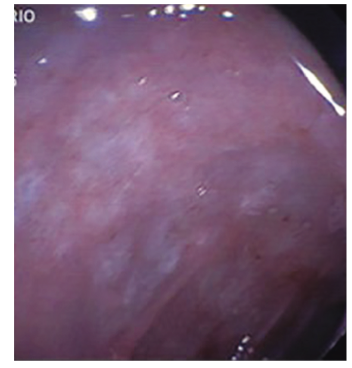

Debido a los hallazgos no concluyentes se decide repetir la videoendoscopía digestiva alta. En esta ocasión se informa que tras progresarse hasta la cuarta porción del duodeno se observan pliegues engrosados, mucosa eritematosa y friable, recubierta por placas blanco-amarillentas, tomándose múltiples biopsias (cinco) (Figuras 3 y 4).

En el estudio endoscópico del tubo digestivo puede visualizarse en la región posbulbar del duodeno y a nivel del yeyuno una mucosa pálida y despulida alternando con zonas erosionadas, eritematosas o friables. Puede presentar además linfangiectasia, que torna la mucosa de color amarillo pálido.29, 30 En la segunda endoscopía se visualizó una mucosa eritematosa y friable, recubierta por placas blanco-amarillenta.